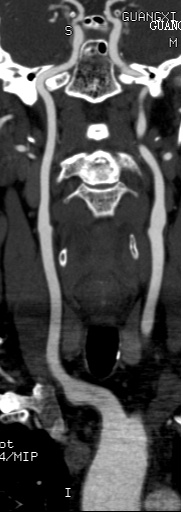

CT全称是Computed Tomography(计算机断层成像),与普通X线一样,都是以X线穿透人体为基础,不过是分层连续扫描,形成断层图像,没有重叠,能看清楚器官之间的空间位置关系,也可以通过计算机进行后处理,得到曲面重组、最大密度投影法、容积再现技术、CTA等不同应用的图像。缺点是:辐射剂量相对大,价格贵。

曲面重组图像

最大密度投影